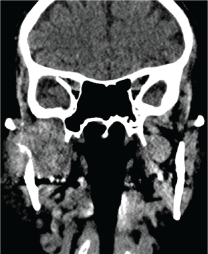

A new panoramic radiography revealed the extensive advance of the osteolytic process that affects the right mandibular condyle. A craniofacial CT demonstrates the total osteolysis of the right temporomandibular region, occupied by a 3.6-2.8 cm mass in the infra temporal fossa and right pterygomaxillary space (Figure 4). Through preauricular end aural approach the lesion is accessed (Figure 5) obtaining an amorphous, solid, not vascularized tissue sample that is sent to differed biopsy; reporting a moderately differentiated adenocarcinoma, characterized by a solid cellular mass that resemble glandular parenchyma with scarce duct-like structures spread all over the tissue (Figure 6). Immunohistochemical analysis mean to find the primary tumor, reveal positive results to Cytokeratin 7 (CK7+), compatible with an adenocarcinoma. At this point, cannot be ruled out the possibility for a salivary gland adenocarcinoma of parotid origin against a possible metastatic adenocarcinoma, of probably lung origin. The Cluster of differentiation 10 (CD10) for renal origin is also requested because of focal areas of clear cells, with negative response. A computed tomography with contrast of abdomen, chest and pelvis is requested, where a large mass of soft tissue density and irregular borders of 6 × 5.5 cm, with necrotic areas inside is observed in the right pulmonary lobe, widely contacting the pleura at the para mediastinal level, remarking multiple pulmonary nodules and regional adenopathy's (paratracheal, subcardial and supraclavicular) (Figure 7).

Figure 4: The image show a coronal cut CT. Demonstrates a mass 3.6-2.8 cm that involves the temporomandibular region, the infra temporal fossa and right peterigomaxillary space. The image shows the mass infiltrating in the condylar and ramus bone (osteolytic process). View Figure 4